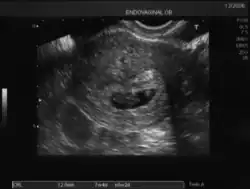

Ecografía de 7 semanas -

Los signos positivos de certeza de un embarazo consisten en poder demostrar sin error la presencia de estructuras embrionarias mediante ultrasonido y otras imágenes radiológicas.

Rastreo ecográfico

En cualquier momento del embarazo, en especial en presencia de un feto maduro en la segunda mitad del embarazo, es posible demostrar por ecografía transabdominal bidimensional o tridimensional tanto sus partes anatómicas como el saco vitelino.